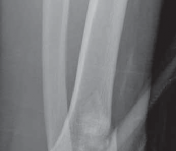

### FIG 3 • Low-energy spiral 43-A type fracture.

24. In contrast to high-energy patterns, rotational injuries ( FIG 3) cause spiral fractures of the distal tibia and fibula originating at the articular level. Intra-articular injury, if present, is typically simple and without comminution or impaction. NATURAL HISTORY